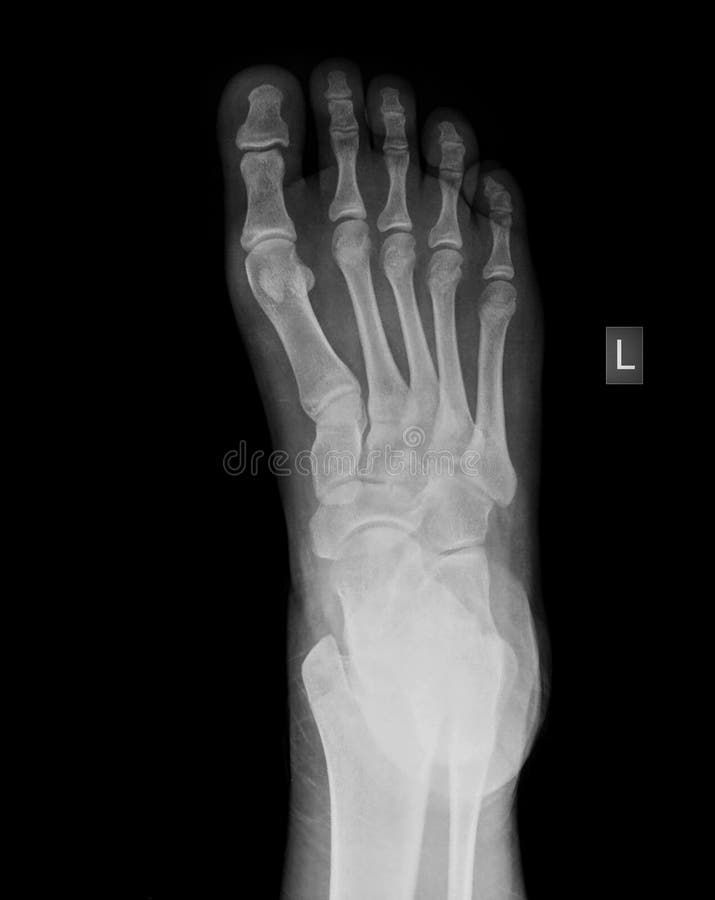

Types Of Foot X Rays . The series is often utilized in. this view demonstrates the location and extent of fractures in the foot, joint space abnormalities, soft tissue. the foot series is comprised of a dorsoplantar (dp), medial oblique, and a lateral projection. these bones include the tarsal bones in your ankle, the metatarsal bones in the front of your foot, and the phalanges in your toes. The image displays the soft tissues and bones of your.

The series is often utilized in. the foot series is comprised of a dorsoplantar (dp), medial oblique, and a lateral projection. The image displays the soft tissues and bones of your. this view demonstrates the location and extent of fractures in the foot, joint space abnormalities, soft tissue. these bones include the tarsal bones in your ankle, the metatarsal bones in the front of your foot, and the phalanges in your toes.